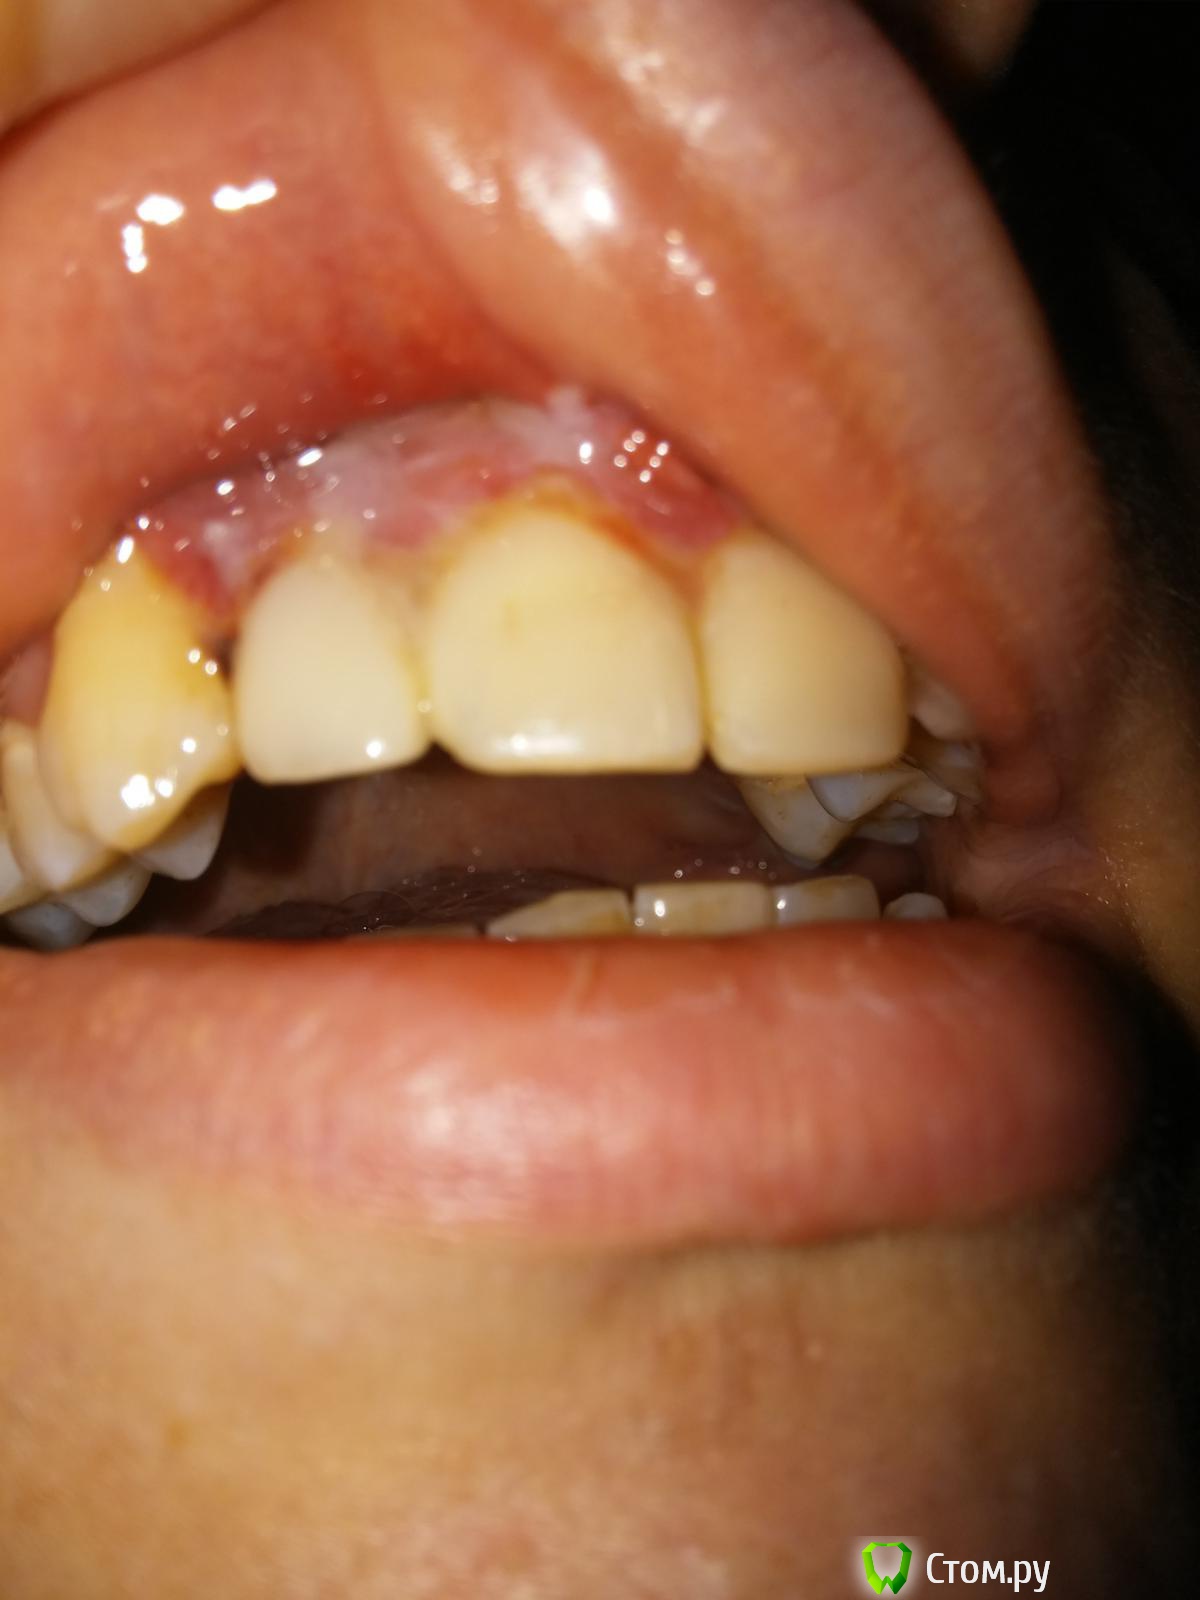

Виталий435 Опубликовано 23 августа, 2014 Поделиться Опубликовано 23 августа, 2014 Несколько лет назад мне запломбировали 4 передних верхних зуба около десны. В последнее время десна около этих 4 зубов воспалилась, врач сказал, что пломбы установлены плохо и упираются в десну. 3 дня назад мне переделали все пломбы, десна много кровила в процессе. Уже в конце процедуры десна была опухшей и опухлость так и не проходит. Это нормально? При начале лечения десна была воспалённой, но не опухшей. Также сейчас есть небольшая боль при движении верхней губой. Ссылка на комментарий

Виталий435 Опубликовано 23 августа, 2014 Автор Поделиться Опубликовано 23 августа, 2014 Вот. Только вспышка немного исказила цвет, зубы на самом деле выглядят белыми Ссылка на комментарий

red_butler Опубликовано 23 августа, 2014 Поделиться Опубликовано 23 августа, 2014 снимок конечно не ахти, но похоже проблема пародонтологическая. Сходите к пародонтологу Ссылка на комментарий

Виталий435 Опубликовано 23 августа, 2014 Автор Поделиться Опубликовано 23 августа, 2014 вполне, плюс делайте ванночки с 0,05 % хлоргекседином 3-4 р/д а вот эта белая плёнка на десне, это процесс заживления или воспаления? Ссылка на комментарий

red_butler Опубликовано 23 августа, 2014 Поделиться Опубликовано 23 августа, 2014 а вот эта белая плёнка на десне, это процесс заживления или воспаления?похоже на фибринозный налет, фибрин - элемент крови. Ссылка на комментарий

faity Опубликовано 23 августа, 2014 Поделиться Опубликовано 23 августа, 2014 (изменено) фибринозный налет в данном случае результат травмы, отек мягких тканей связан с ней же, нужно смотреть очно и ОПТГ сделатькогда ванночки будете делать хлоргексидиновые, не увлекайтесь, р-ор держать во рту по 15-20 сек Изменено 23 августа, 2014 пользователем faity Ссылка на комментарий